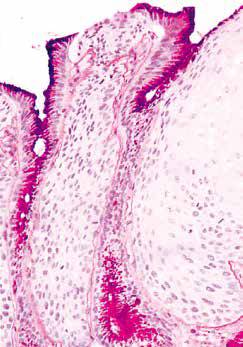

食管黏膜层由非角化性复层鳞状上皮、固有层及黏膜肌层构成。其中,鳞状上皮分为基底层、棘层和表面细胞层。

食管中段。食管黏膜由表面的上皮层、中间的固有层及下面的黏膜肌层构成,黏膜肌层由纵行平滑肌束构成。

食管中段。食管上皮基底层细胞缺乏糖原,与其上层覆盖的糖原丰富细胞易于鉴别(PAS染色)。

正常食管鳞状上皮黏膜中还可见一些其他类型的各种细胞,包括黑色素细胞、Merkel细胞、上皮内单核细胞、淋巴细胞等。

由于淋巴细胞在上皮细胞间交错分布,其细胞核变得扭曲,可能会与中性粒细胞的细胞核相混淆。这种形态的细胞称为波浪细胞(squiggle cell)或核形不规则的上皮内细胞(intraepithelial cells with irregular nuclear contours)。

波浪细胞。食管上皮内有许多淋巴细胞,其中一些呈“波浪”状(箭头)。此外,细胞间间隙扩大,使棘突非常明显,部分上皮细胞交界处形成小“空泡”(右上方易见)。需要注意的是,不要将核周空泡/ 细胞质收缩或核旁空泡当成食管下段细胞间隙增宽 (dilated intercellular spaces,DIS)。